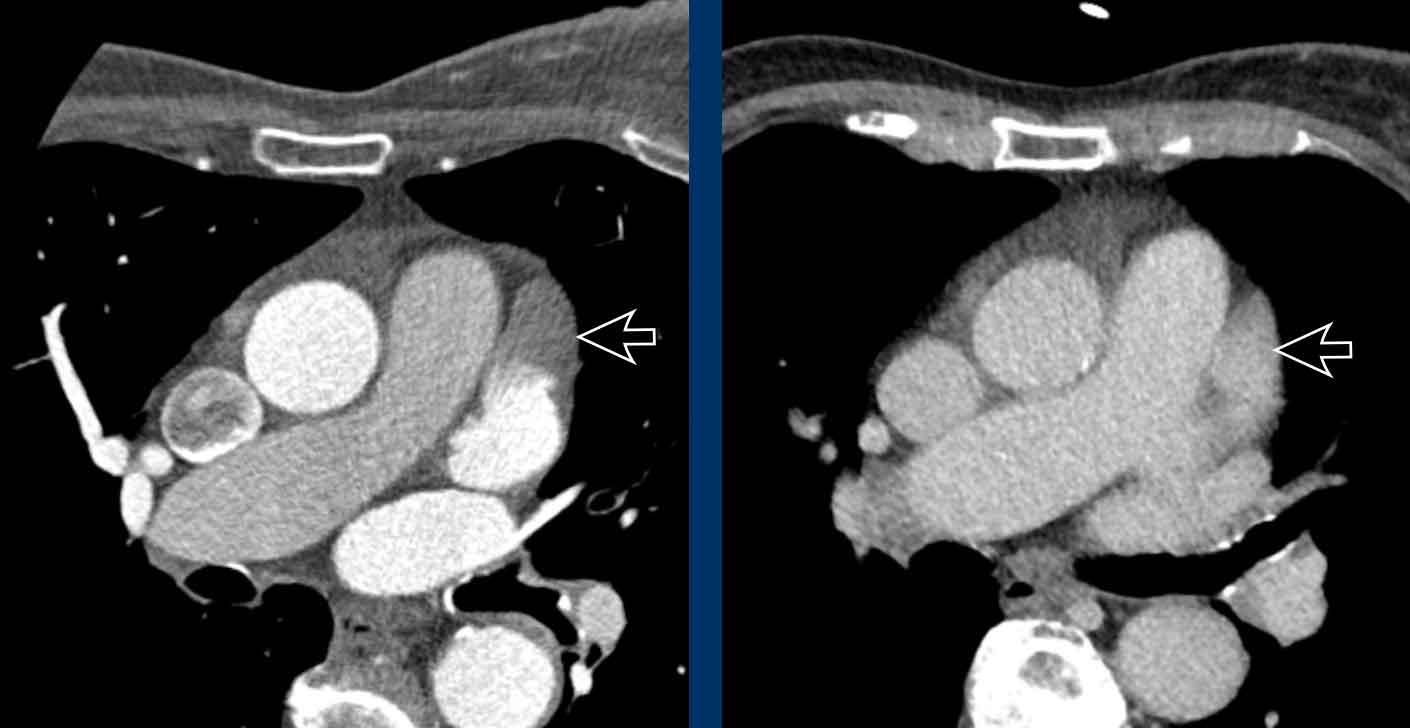

Hình ảnh

Bệnh nhân này được lên kế hoạch cắt thùy trên phải do ung thư phổi và bất thường mạch máu này ban đầu đã bị bỏ sót trên hình ảnh CT.

Những hệ quả trong phẫu thuật của bất thường như vậy nhấn mạnh tầm quan trọng của việc không bỏ sót các biến thể này.

PAPVR bên trái phát hiện tình cờ với dẫn lưu trên tim của máu từ thùy trên trái vào tĩnh mạch tay đầu trái (các mũi tên).